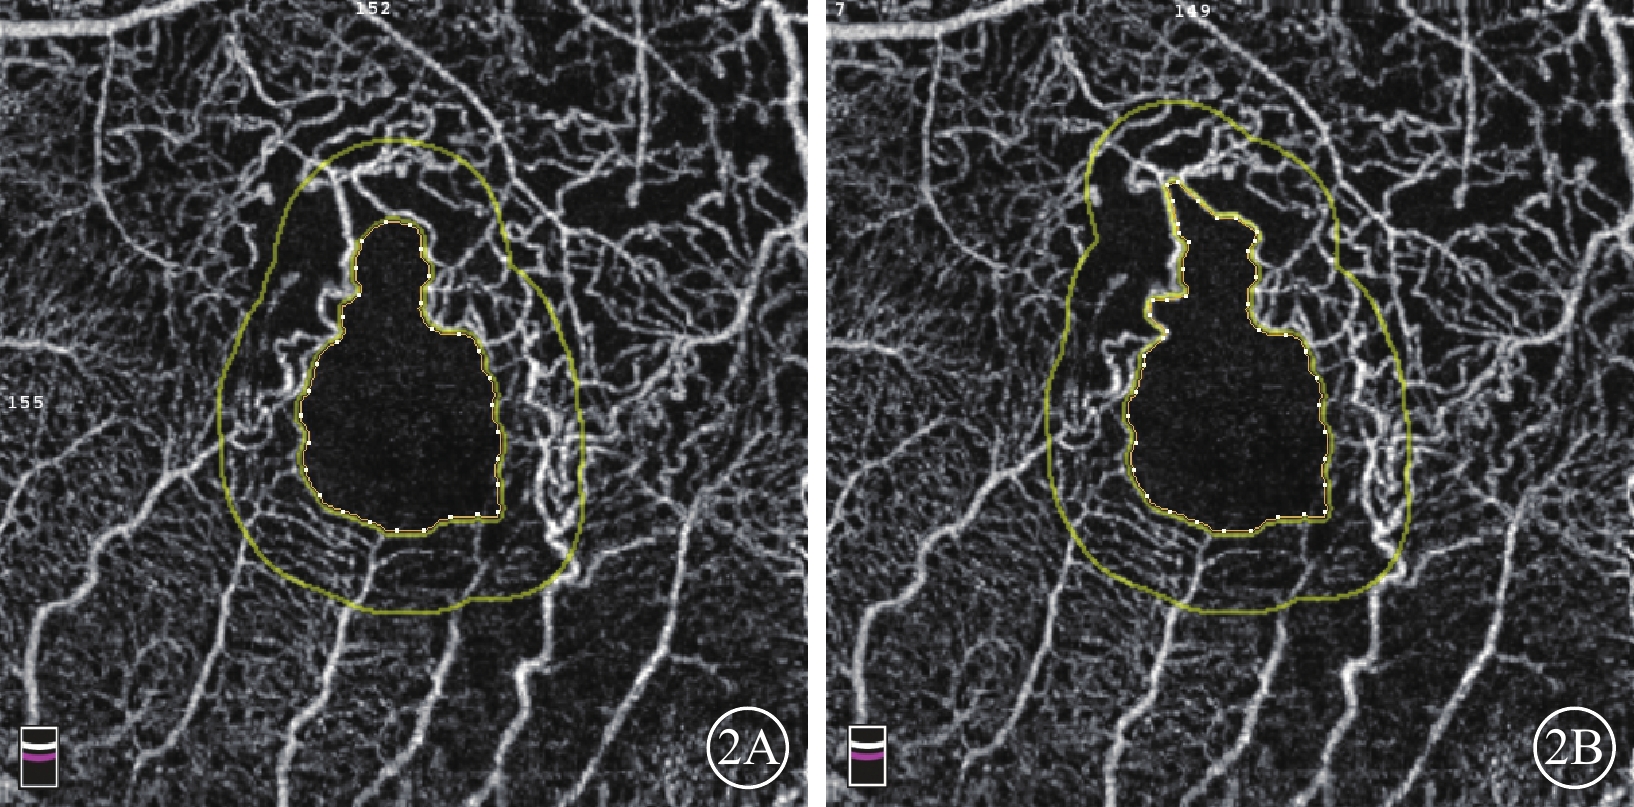

采用美國Optovue公司RTVue-XR Avanti OCT儀行黃斑區OCTA檢查。檢查由同一位熟練醫生獨立操作完成。掃描程序AngioVue Retina,掃描范圍3 mm×3 mm,A掃描為70 000次/s,光源波長840 nm,頻寬50 nm。每次A掃描包含304×304條B掃描線。所采集數據采用系統自帶軟件進行分析,并自動合成4張不同層面OCTA圖像,即SCP、DCP、外層視網膜及脈絡膜毛細血管層。采用設備自帶軟件(OCTA血流量化標準2.0版)測量并計算全層視網膜FAZ面積、PERIM、非圓度指數(AI)以及FAZ范圍300 μm寬度內的血流密度(FD-300)(圖1A),中心凹視網膜厚度(CRT),中心凹SCP視網膜血流密度(SFVD)、中心凹DCP視網膜血流密度(DFVD),BRVO病灶所在區域SCP半側視網膜血流密度(SHVD)、DCP半側視網膜血流密度(DHVD)(圖1B,1C)。SCP為內界膜(ILM)上3 μm至內叢狀層(IPL)下15 μm,包含視神經纖維層和節細胞層;DCP為IPL下15~70 μm,主要包含內核層。全層視網膜是從ILM至內叢狀層邊界之間的視網膜各層;水腫腔位于ILM與IPL之間導致斷面分層發生錯誤時,給予手動調整并記錄調整后的數據。AI=PERIM/等面積標準圓周長。75只眼中,28只眼(37.33%)FAZ面積自動識別區域與FAZ真正呈現區域不符,給予手動調整并記錄(圖2)。

圖2

BRVO患眼OCTA像。2A示軟件自動繪制的FAZ(內圈不規則黃色線內區域),可見拱環上方仍有部分無血管區;2B示手動修改后的FAZ(內圈不規則黃色線內區域)

圖2

BRVO患眼OCTA像。2A示軟件自動繪制的FAZ(內圈不規則黃色線內區域),可見拱環上方仍有部分無血管區;2B示手動修改后的FAZ(內圈不規則黃色線內區域)

采用美國Optovue公司RTVue-XR Avanti OCT儀行黃斑區OCTA檢查。檢查由同一位熟練醫生獨立操作完成。掃描程序AngioVue Retina,掃描范圍3 mm×3 mm,A掃描為70 000次/s,光源波長840 nm,頻寬50 nm。每次A掃描包含304×304條B掃描線。所采集數據采用系統自帶軟件進行分析,并自動合成4張不同層面OCTA圖像,即SCP、DCP、外層視網膜及脈絡膜毛細血管層。采用設備自帶軟件(OCTA血流量化標準2.0版)測量并計算全層視網膜FAZ面積、PERIM、非圓度指數(AI)以及FAZ范圍300 μm寬度內的血流密度(FD-300)(圖1A),中心凹視網膜厚度(CRT),中心凹SCP視網膜血流密度(SFVD)、中心凹DCP視網膜血流密度(DFVD),BRVO病灶所在區域SCP半側視網膜血流密度(SHVD)、DCP半側視網膜血流密度(DHVD)(圖1B,1C)。SCP為內界膜(ILM)上3 μm至內叢狀層(IPL)下15 μm,包含視神經纖維層和節細胞層;DCP為IPL下15~70 μm,主要包含內核層。全層視網膜是從ILM至內叢狀層邊界之間的視網膜各層;水腫腔位于ILM與IPL之間導致斷面分層發生錯誤時,給予手動調整并記錄調整后的數據。AI=PERIM/等面積標準圓周長。75只眼中,28只眼(37.33%)FAZ面積自動識別區域與FAZ真正呈現區域不符,給予手動調整并記錄(圖2)。

圖2

BRVO患眼OCTA像。2A示軟件自動繪制的FAZ(內圈不規則黃色線內區域),可見拱環上方仍有部分無血管區;2B示手動修改后的FAZ(內圈不規則黃色線內區域)

圖2

BRVO患眼OCTA像。2A示軟件自動繪制的FAZ(內圈不規則黃色線內區域),可見拱環上方仍有部分無血管區;2B示手動修改后的FAZ(內圈不規則黃色線內區域)